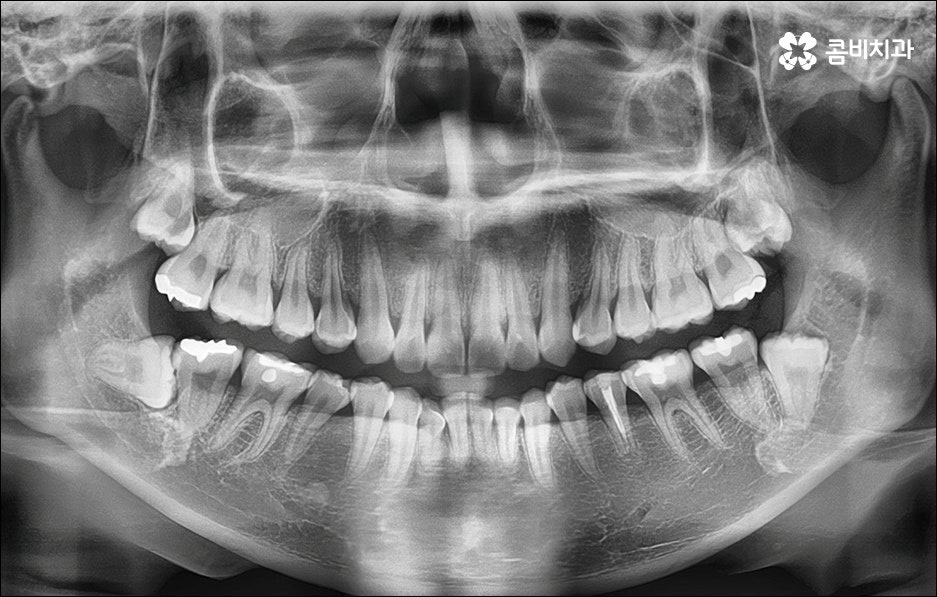

치열이 불규칙하여 기능적 심미적인 불편을 겪는 분들 중에 교정 치료를 고민하시는 분들이 많이 있습니다. 특히 앞니는 다른 치아보다 훨씬 외부에 잘 드러나므로 대화하거나 웃을 때 만약 앞니 사이가 벌어져 있거나 앞니 돌출 이 된 경우, 비틀어진 경우에는 신경이 많이 쓰일 수 있는데요. 하지만 막상 교정을 시작 하려고 하면 기간이 오래 걸리는 것 때문에 또는 치료 과정 자체에 부담을 느껴서 망설이시는 분들도 있을 수 있어요. 이때 앞니 외 다른 치아 배열 또는 위아래 교합에는 별다른 이상이 없다면 문제가 있는 앞니만 부분교정으로 치료할 수 있으니 이에 대해서 한 번 알아보시면 도움이 되실 거예요.

부분교정은 짧은 기간에 모든 치아가 아닌 특정 치아만 집중적으로 교정하는 것으로, 예를 들어 앞니 돌출 을 개선하기 위해 앞니와 그 옆의 치아까지 6~8개의 치아에만 브라켓을 장착하여 교정 치료를 하는 것을 의미하고 있어요. 비교적 간단한 과정이라고 생각하실 수 있으나 다른 치아에는 영향을 주지 않으면서 주변 치아와 앞니의 이동량을 고려하여 교합을 세밀하게 조정하고 전체 균형을 맞춰나가야 하는 만큼 의료진의 높은 숙련도가 필요한 과정이라고 할 수 있는데요.

상황에 따라 다르지만 전체 교정이 통상적으로 1년에서 2년 반 정도의 기간이 걸리는 데 반해서 앞니 돌출 부분교정은 3~6개월 정도의 짧은 기간이 소요되며 발치에 대한 걱정이나 비용에 대한 부담도 줄여주기 때문에 많은 분들이 가능하다면 부분 교정 치료를 받고 싶으실 수 있어요. 하지만 누구나 부분 교정 치료가 가능한 것은 아니며 앞니 돌출 원인과 현상에 대한 꼼꼼한 분석을 통해 가능한지 여부, 치료 시기, 방법 등이 모두 달라지기 때문에 먼저 정확한 검진 및 충분한 상담부터 진행해 보시는 것을 추천드리고 있습니다. 또한 환자 개개인의 상황을 정확하게 검진하고 맞춤 플랜을 세울 수 있는 정밀 장비와 꼼꼼한 사후관리 시스템을 갖추고 있는 치과에서 무리하지 않게 치료 받는 게 중요하다는 점을 명심하시길 바라고 있어요.

앞니가 튀어나오는 원인은 무엇일까요? 앞니 돌출 의 원인은 치아 크기가 큰 데 반해서 골격이 많이 작거나 상하악골 크기 차이가 많이 나는 것처럼 유전적인 요소에 기인하는 경우가 많으나 후천적인 생활 습관으로 인해서 발생하고 강화될 수도 있기 때문에 주의하실 필요가 있어요. 예를 들어 어릴 때 부터 손톱을 물어뜯거나 손가락을 자주 빠는 습관, 혀로 앞니를 밀면서 빼물곤 하는 습관을 가지고 있었다면 이로 인해 앞니가 튀어나올 수도 있는 거예요. 또한 축농증, 비염 등의 질환으로 인해 구호흡을 하게 되었다면 이것이 원인으로 작용할 수도 있으니 필요하다면 이비인후과와 협진을 하는 등 원인파악과 개선을 전반적으로 함께하시길 권유드리고 있어요.

만약에 앞니 돌출 이 각도만의 문제라면 이를 교정하기 위한 치료는 좀 더 간단하게 끝날 수 있습니다. 말씀드렸던 것처럼 상황에 따라 보다 빠른 부분교정을 통해 앞니만 교정 치료를 진행할 수도 있을 거예요.

하지만 보통은 돌출된 앞니 뿐 만 아니라 골격적인 부분이 원인이 되는 경우가 많으며 이런 경우에는 상태에 맞게 전체적으로 교정을 진행하여야 교합이 올바르게 되고 입매가 전체적으로 균형감 있게 개선될 수 있어요. 이런 경우에 골격적인 원인을 무시한 채 무리하게 치아의 각도만 안쪽으로 넣으려고 하면 자칫 옥니가 될 수도 있기 때문에 이러한 부작용을 막기 위해서도 환자분들의 상황을 정확하게 검진하고 그에 맞는 교정 플랜을 세우는 것이 필요한 거예요. 물론 부정교합 정도가 심각하고 골격적인 원인이 이미 굳어진 경우와 같이 수술이 함께 필요한 케이스도 있을 수 있으나 교정 치료만으로도 튀어나온 앞니가 들어가면서 자연스럽고 부드러운 인상으로 바뀌는 경우도 많으니 먼저 검진과 상담부터 꼼꼼하게 진행해 보시길 권유드리고 있습니다. 특히 개개인의 치열, 교합, 잇몸 상태, 구강구조 등을 면밀하게 파악하고 그에 따른 정확한 치료 계획을 수립할 수 있는 경험 많은 의료진과 함께 하는 것이 중요할 수 있어요.

골격적인 부분이 원인이 되는 경우 치료 시기 역시 중요할 수 있는데요. 성장기가 끝나고 잇몸뼈가 굳어지기 전에 상악과 하악의 균형잡힌 발달을 유도하는 것이 필요하기 때문에 윗턱에 비해 아래턱이 많이 작다면 2차 성징이 나타나기 전에 치료를 시작하는 것이 좋을 거예요. 2차 성장 시기는 성별 (여자 아이가 남자 아이보다 빠름) 및 개인마다 차이가 나지만 보통 10~12세 사이이니 필요하다면 이때 아이와 함께 치과에 내원하시길 추천드리고 있는데요. 돌출입 구조에 있어서 유전의 영향은 30% 정도이니 만약에 부모님께서 상악골이 돌출된 부정교합을 가지고 있다면 더욱 관심을 가지고 아이의 치열을 관찰하셔서 치료 시기를 조율해 보시는 게 좋을 거예요. 또한 상황에 따라 교정 치료 전에 충치나 잇몸을 먼저 치료하는 과정이 필요할 수 있으니 시작 시기나 전체 기간, 방법 등 자세한 사항들에 대해서 면밀한 검진 후 충분하게 상담부터 받아 보시길 권유드리고 있습니다.